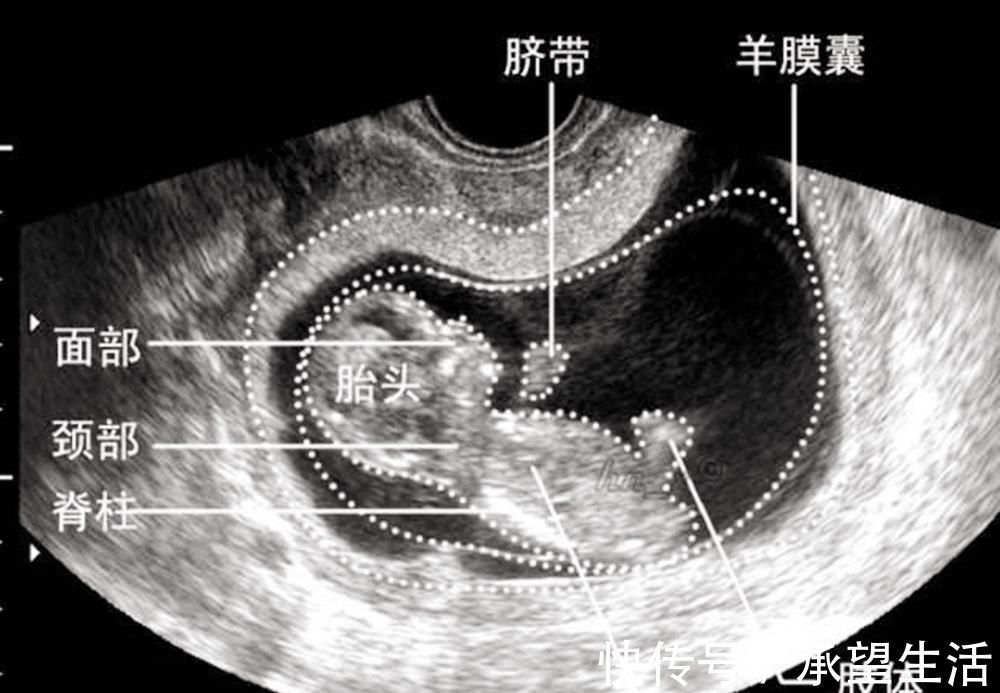

等到怀孕第8周的时候,从B超上看就能清楚地看到发育的形态,甚至还会有胎动,这个时候就预示着正式从胚胎期进入到了胎儿时期(孕9-分娩)。

这个时候的胚胎发育开始出现眼睛、嘴巴、耳朵的轮廓,脸部的模样基本形成,而胎盘和脐带也开始工作。